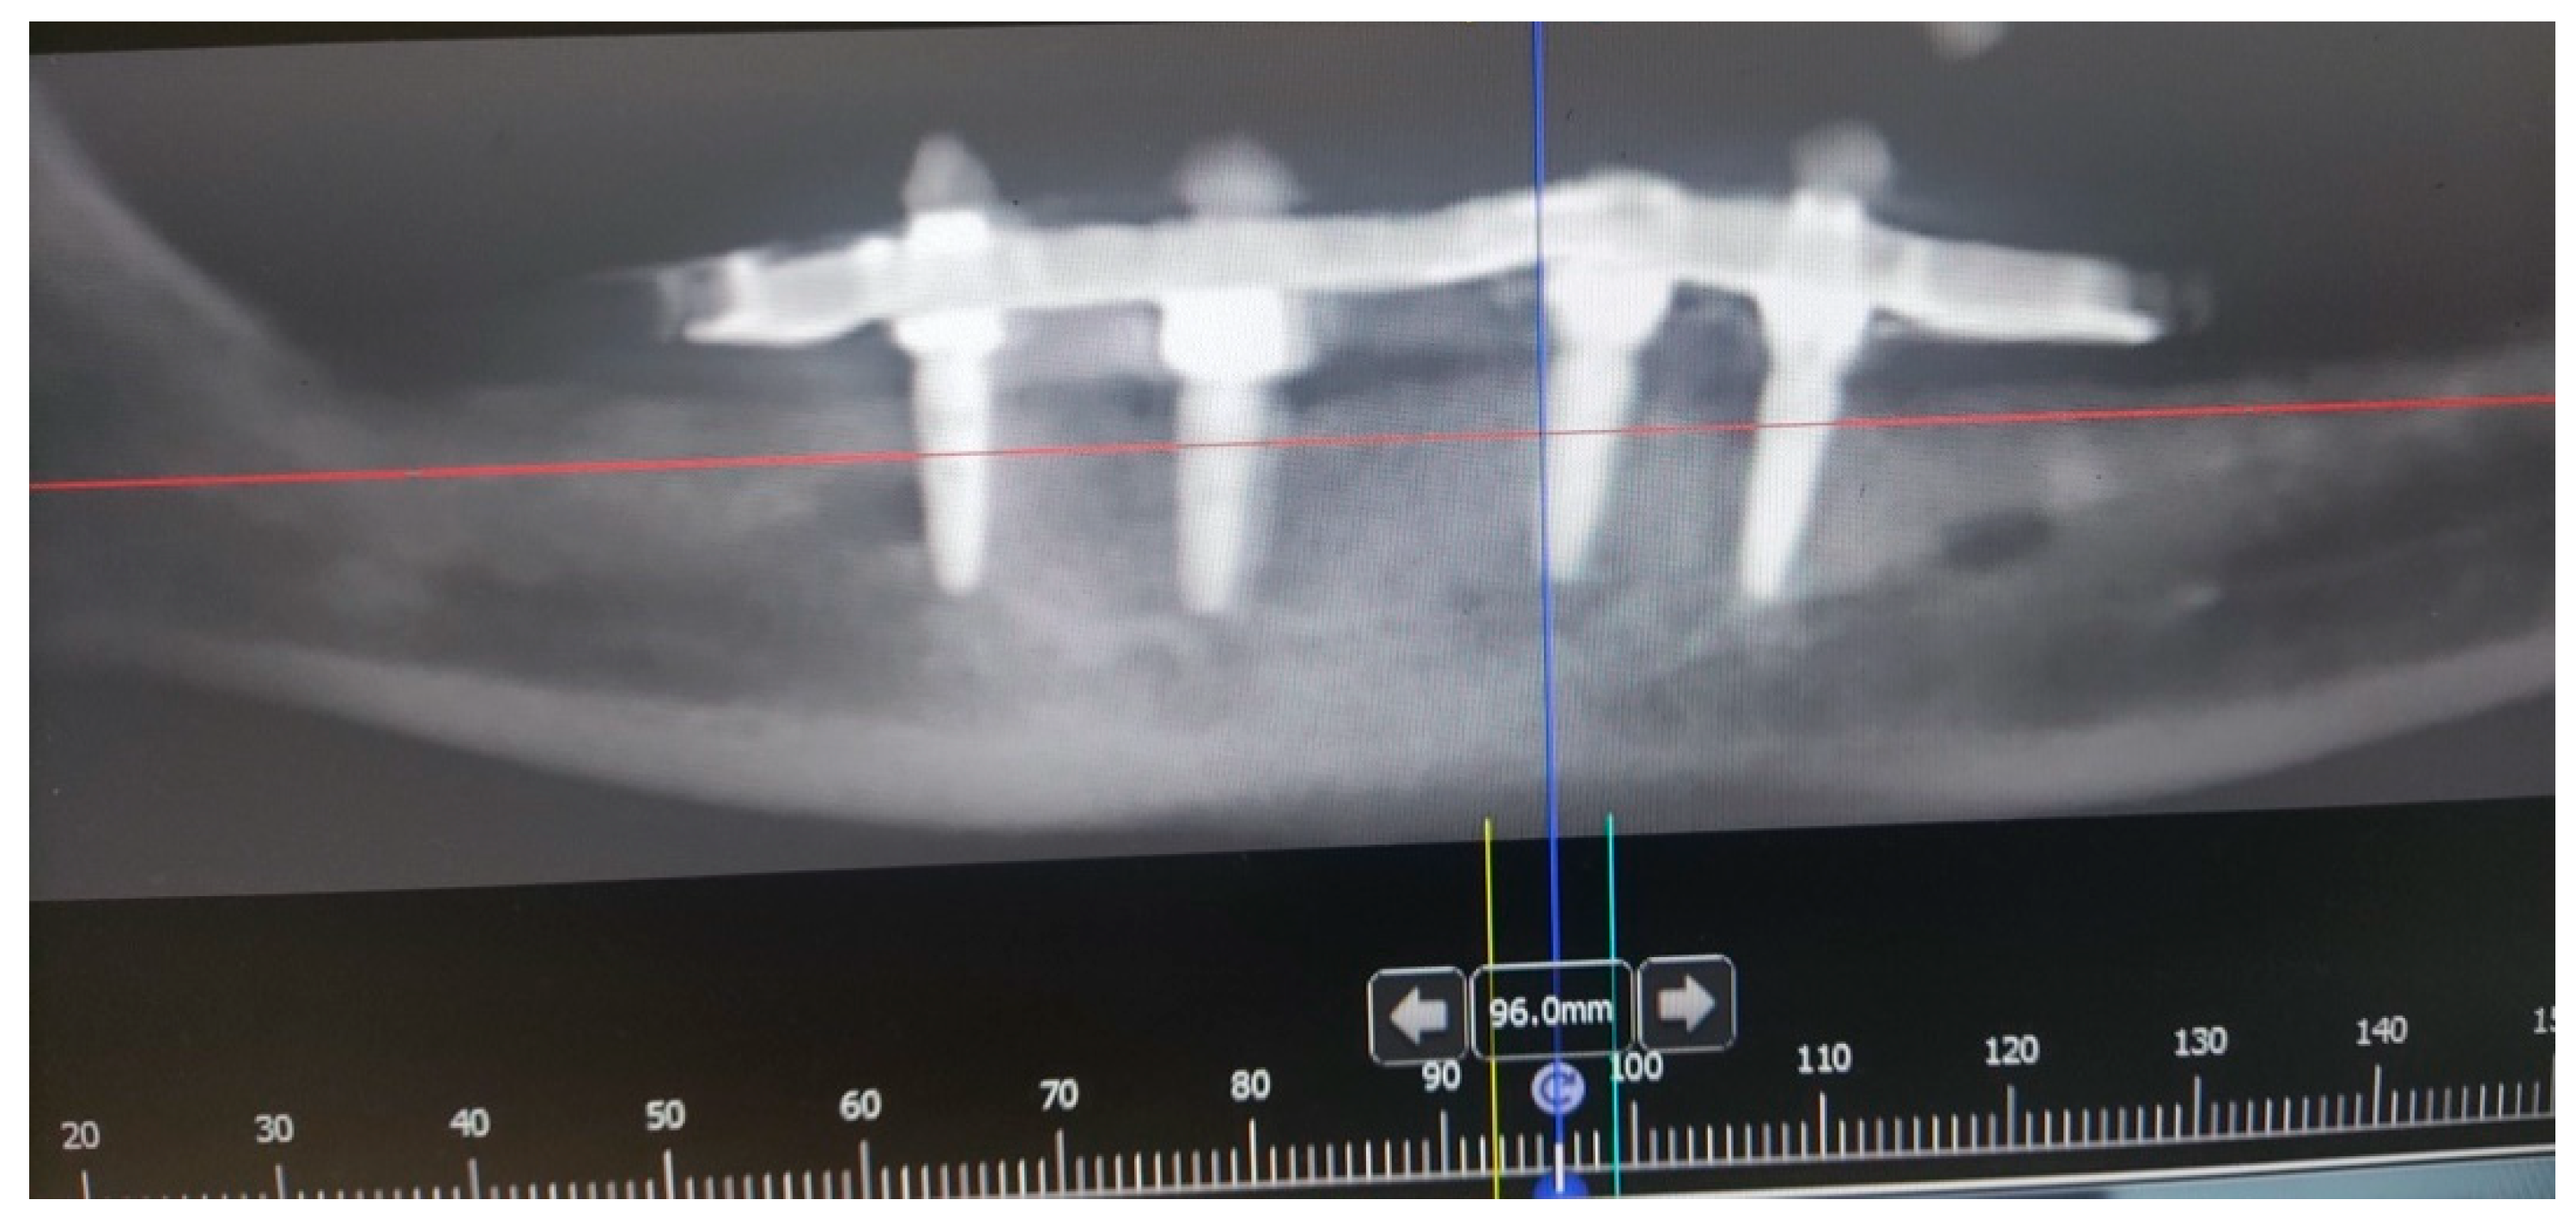

A male 70-year-old patient came to the Department of Oral Surgery, University Hospital Centre Zagreb with a voluminous fibrous mass in the distal region of the left mandible (Figure 1). The patient has two acrylic bridges on four implants. The implants were placed six months prior to admission to the clinic, before the patient noticed the appearance of the mass. The acrylic bridges are 3 months old. The patient states feeling “swelling in the back part of the left mandible three months before coming in for a checkup”. Panoramic radiograph and CBCT did not show any radiolucency, radiopaque areas or signs of periimplantitis around the implants in the bone (Figure 2). The lesion has a smooth surface, with no ulcerations. It was on a broad base connected, with the sublingual anatomical region. The patient has poor oral hygiene, smokes and consumes alcohol: about two to three glasses of wine or beer a day. The palpation of the mass indicated that it was fixed to the alveolar crest of the left mandible on a wide base and was spreading to the left sublingual area. The measured size of the mass was 3.5 × 2 cm. After conducting a clinical examination, the differential diagnosis was possible irritation fibromatosis, peripheral gigantocellular fibroma or peripheral ossifying or non-ossifying fibroma, as well as a malignant mass, and the final diagnosis will be reached after the final PHD analysis. The final decision was an excision in toto (Figure 3). The mass was approached and the layers of submucosa were divided with a scalpel and an electro knife. During operation, it was noticed that the mass has a belonging artery connected to the left sublingual area. The artery was ligated with a resorbing thread 4/0 and the mass underwent complete excision (Figure 4). Parts of the flap were left to heal per secundam, but most of the incision towards the sublingual region was stitched with a non-resorbing silk thread 4/0 (Figure 5 and Figure 6). A full hemostasis was achieved by electrocauterization of the bleeding areas. The excison was performed under local anesthesia. Clinical, medical examination and removal of sutures were performed seven days after surgery (Figure 7).

Figure 2. Orthopantomogram of the lower jaw of the patient.